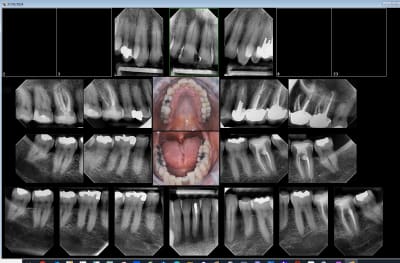

Capteur RVG (filaire) sans hésitation. Moins cher, gain de temps, meilleure qualité d'image et meilleure ergonomie avec les angulateurs Xcp-Ora.

Chez certains patient, il y a en effet moins de nausées avec les plaques. Et encore, les capteurs (Taille 1, généralement) étant moins larges que les plaques (Taille 2, le plus souvent possible), je ne suis pas convaincu.

Tiens status meilleur rapport qualité - prix capteur taille 2 isensor woodpecker 1500 balles camera MD960 150 balles. Qui dit mieux ?

sinon avec le film chez les jeunes tu peux faire ca, pour le depistage des caries:

Tu peux faire ça aussi.